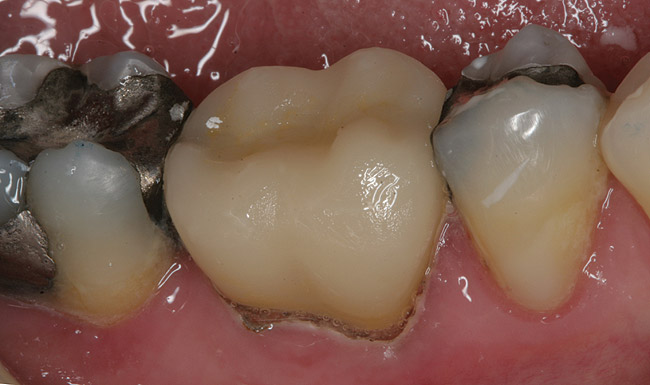

Figure 8 Preoperative view of a gold crown requiring replacement as a result of secondary decay.

Figure 8

Figure 9 The previous gold crown was digitally scanned before removal. The tooth was prepared, rescanned, and then a lithium-metasilicate restoration was milled.

Figure 9

After finishing, external staining was applied.

Figure 10

Figure 11 Postoperative view. Before the crown was cemented, it had been placed in a ceramic oven that reached a temperature of 850°C. At this temperature, crystallization of the ceramic occurs, resulting in a change of lithium metasilicate to disilicate.

Figure 11